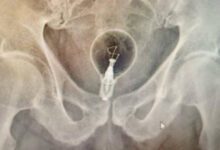

生物學家佩雷拉博士(Dr. Gomes-Pereira)表示,他們花了好幾個小時,才順利測量完翻車魚的體重,由於牠的魚皮厚達20公分,解剖起來也不容易,推測這條魚至少活了20年,但目前科學家依舊不清楚翻車魚壽命究竟多長,另外還發現翻車魚頭部側面有大面積挫傷,認為牠可能曾被漁船撞到而喪命,也呼籲漁民開船時要放慢速度,以免影響海洋野生動物。